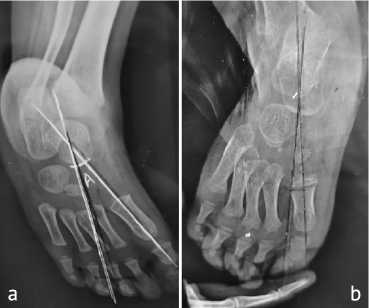

A prepared data collection sheet was used to gather the data for the following variables: demographic data (including age, gender, residency and socioeconomic status); family history (consanguinity of parents, age of father and mother and number of siblings); clinical presentation (including the site of the problem, unilateral or bilateral, and pre-and post-treatment severity) and were evaluated using the Pirani score as determined by an orthopaedic specialist. The patient was referred for radiographic imaging taken in two views: anteroposterior and lateral with and without stress. Each patient underwent radiographic imaging of the affected foot using X-RAY 500 MA (manufactured by GU/USA). Non-Stress Position: The foot is positioned in a neutral alignment with no external manipulation. Stress Position: Manual pressure is applied by the examiner to attempt correction of the deformity during radiography used to differentiate between rigid and flexible deformities. Two types of stress were applied. Abduction stress was used to check the forefoot and midfoot flexibility. Dorsiflexion stress was used to evaluate the hindfoot flexibility and ankle joint range of motion.

To obtain radiographs that ensure consistent pressure, one of the patient's relatives was informed how to apply the stress to capture corrected angles.

Talocalcaneal Angle measures hindfoot alignment since decreased angles indicate residual varus. This angle was measured by obtaining an anteroposterior (AP) radiograph of the foot. Identify the central axis of the talus (line drawn along the talar body and neck) and the central axis of the calcaneus. Measure the angle formed by the intersection of these two lines. The normal value range between 25º and 40º. Below this value indicates residual varus deformity (Fig. 1).

Tibiocalcaneal Angle evaluates ankle position and Achilles tendon flexibility. This angle is measured by obtaining a lateral radiograph of the ankle. Identify the longitudinal axis of the tibia and the axis of the calcaneus. Measure the angle formed at the intersection of these two lines. Between 60º to 90º is the normal value and any increase in this value is considered as equinus deformity (Fig. 2).